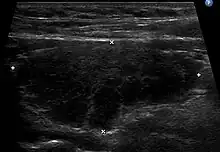

Diagnosis is usually made by detecting elevated levels of antithyroid peroxidase antibodies in the serum, but seronegative (without circulating autoantibodies) thyroiditis is also possible.[54] An ultrasound may be useful in detecting Hashimoto thyroiditis, especially in those with seronegative thyroiditis, due to key features detected in the ultrasound of a person with Hashimoto's thyroiditis, such as "echogenicity, heterogeneity, hypervascularity, and presence of small cysts."[55]

Ultrasound

When patients have normal laboratory values but symptoms of autoimmune thyroiditis, ultrasound plays a role in diagnosis.[16] Images obtained with ultrasound can evaluate the size of the thyroid and further support the diagnosis of autoimmune thyroiditis, reveal the presence of nodules, or provide clues to the diagnosis of other thyroid conditions.[16]